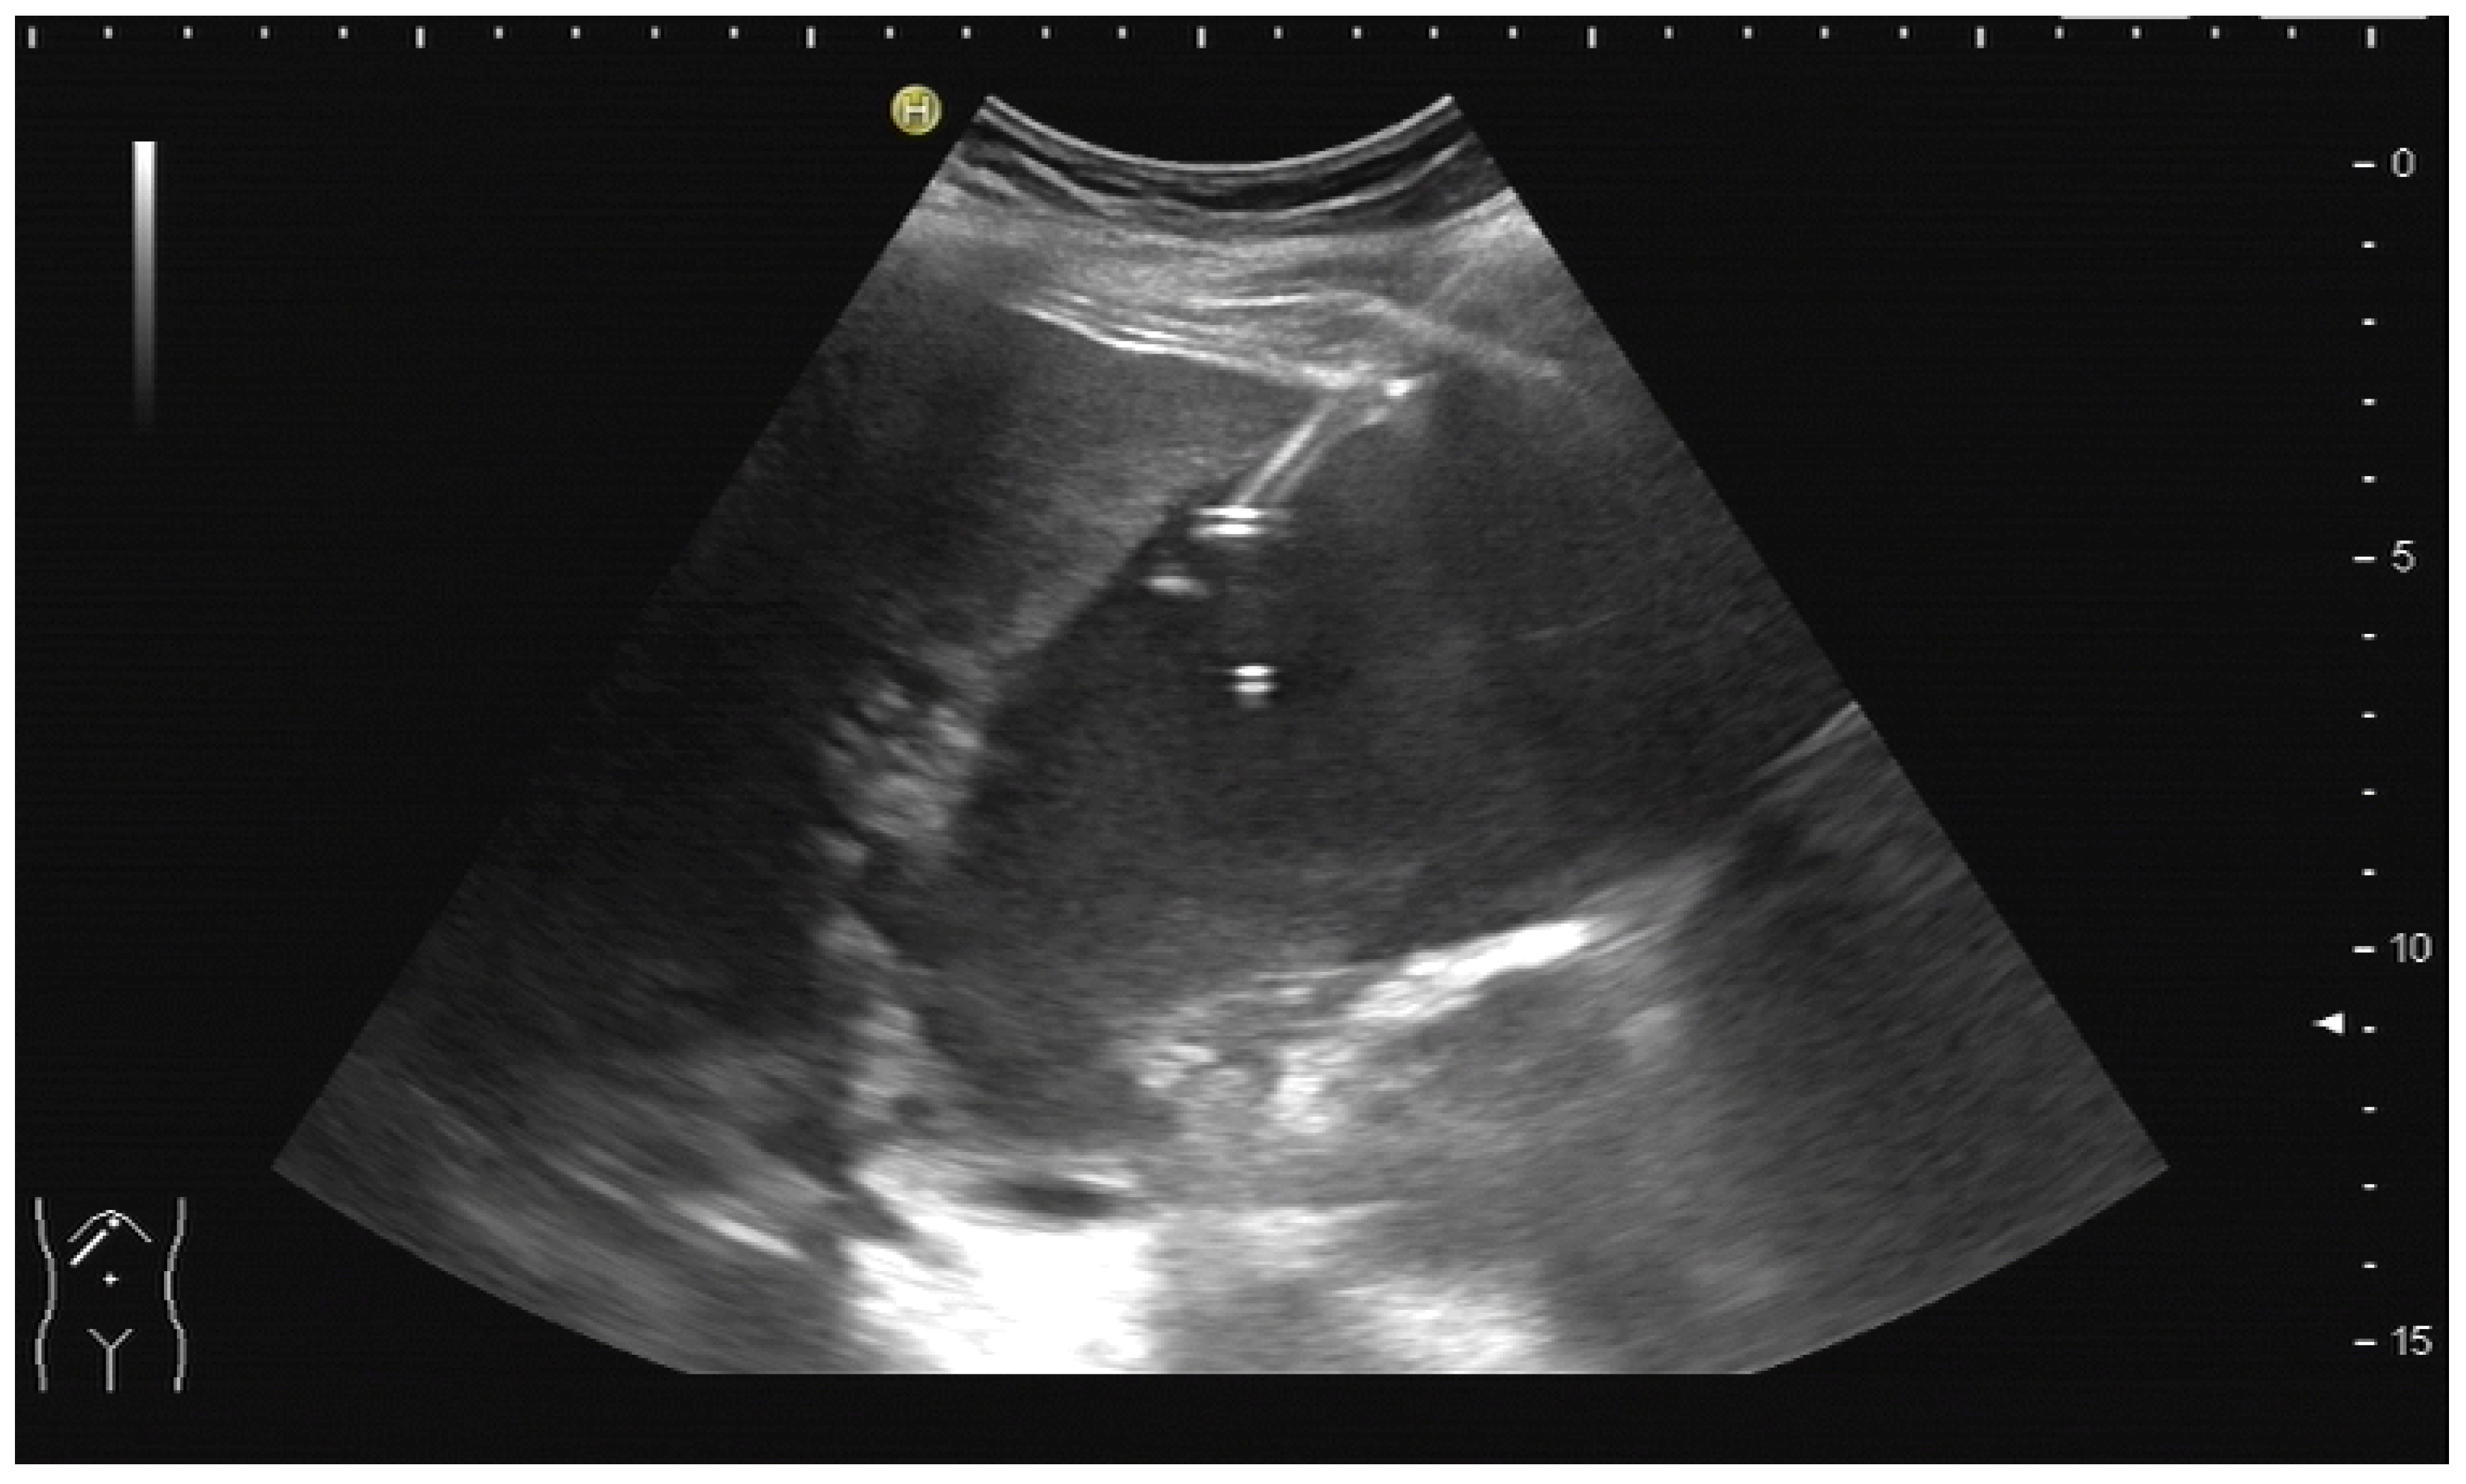

In cases of extrahepatic obstruction, mostly the right liver lobe will be addressed. It is common practice to head for the peripheral branches in Segment V (cf. Figure 3a,b), as from there to the common bile duct, the biliary branches form a harmonic arch, and the forward movement of the guide wire seems unpretentious [3]. However, US guidance allows the puncture of any biliary duct of the right or left liver lobe that can be depicted well (Figure 4a–c).

Figure 4.

(a) A pointed angle between the needle trajectory and a bile duct of Segment V/VI is given; (b) Puncture of a dilated bile duct in Segment IV at a suitable angle. A guide wire with a bended tip should be used to facilitate the correct advancement; (c) A guide wire is placed in a dilated intrahepatic bile duct in Segment III.

If peripheral bile ducts are not dilated and puncture is difficult, sometimes, targeting the central bile ducts and even the common bile duct close to the hilum are the only options to place drainage. When trying to puncture the common bile duct, it is sensible to enter it as proximal as possible to avoid biliary leakage after drain removal. The needle tract should point towards the distal common bile duct (CBD) to facilitate guide-wire advancement (Figure 5).

Figure 5.

Puncture of the CBD in a patient with pancreatic carcinoma. The tip of the needle is seen in the dilated CBD. Pigtail drainage was placed in the CBD, and ten days later, internal drainage by a self-expanding metal stent was placed using a rendezvous technique (percutaneous transpapillary guide-wire advancement and endoscopic stent placement over the wire).